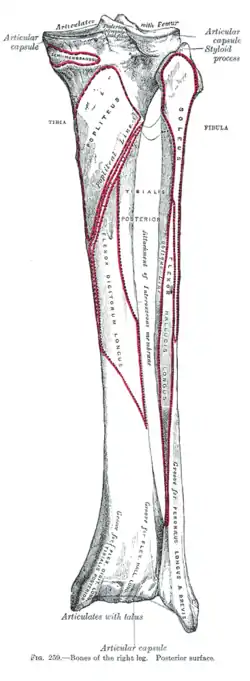

Bones of the right leg. Anterior surface Bones of the right leg. Posterior surface

Bones of the right leg. Posterior surface Dorsum of Foot. Ankle joint. Deep dissection.